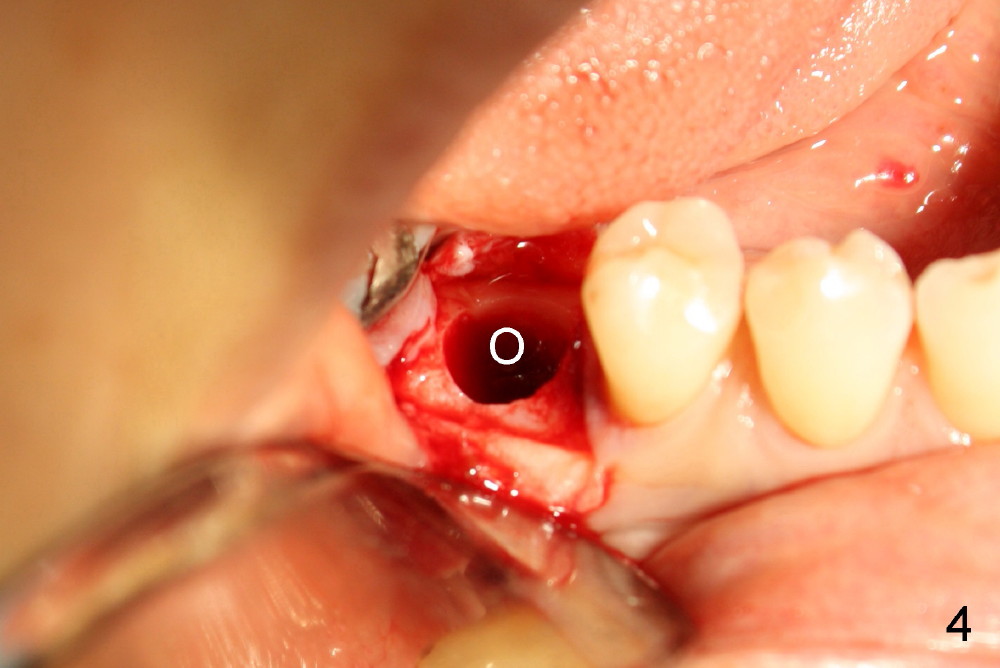

然后小钻头换大钻头,多用冷水冲洗灌注,每次控制好钻头深度,不敢越雷池一步。图四显示直径六毫米的洞(O, osteotomy),颊舌侧骨头好像都有一毫米厚。当洞钻相当大时,不妨用骨匙或者探针(图五:示意图)检查骨壁有没有穿孔,尤其是穿到神经管里(圆圈)。据说碰到神经管时,你会觉得突破感。如果手脚和脑子都很笨,你可能根本察觉不到。比较客观的迹象是出血比较明显。这时可能不要继续钻孔,选择短粗的钻头以及植牙,或者悬崖勒马,术后让病人服用激素减少水肿。